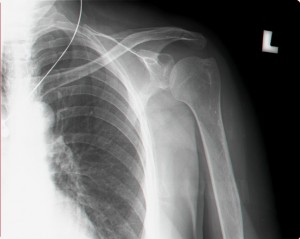

נ.מ לפני טיפול בגלי הלם:

כתף קפואה               טיפול בכתף קפואה